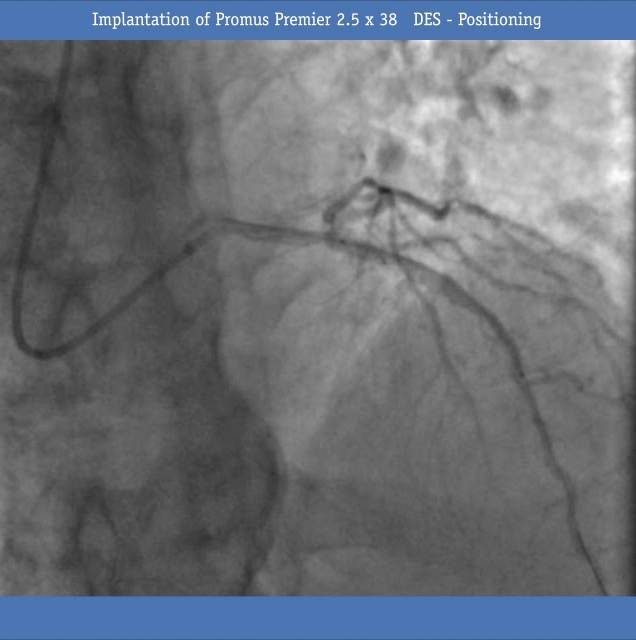

• Next, a Promus Premier 2.5 x38 DES was implanted (Figure 4) and inflated (Figure 5) and post dilated with a non-compliant balloon 2.5x20 mm